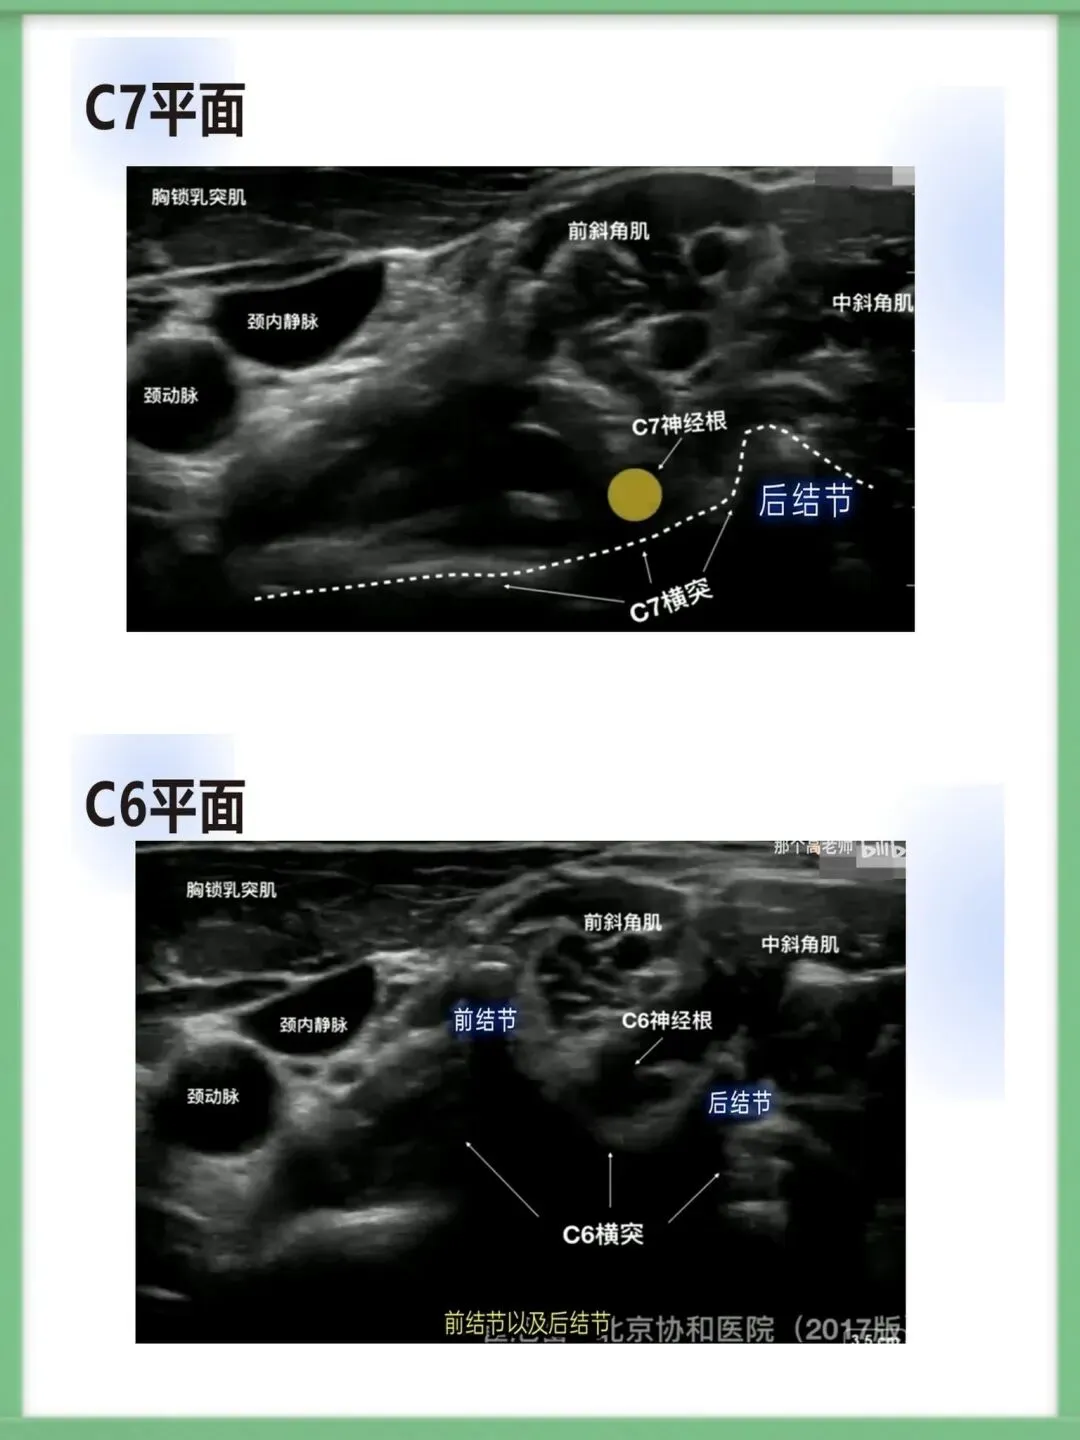

>星状神经节阻滞ppt模板(共25页)

星状神经节阻滞ppt模板(共25页)